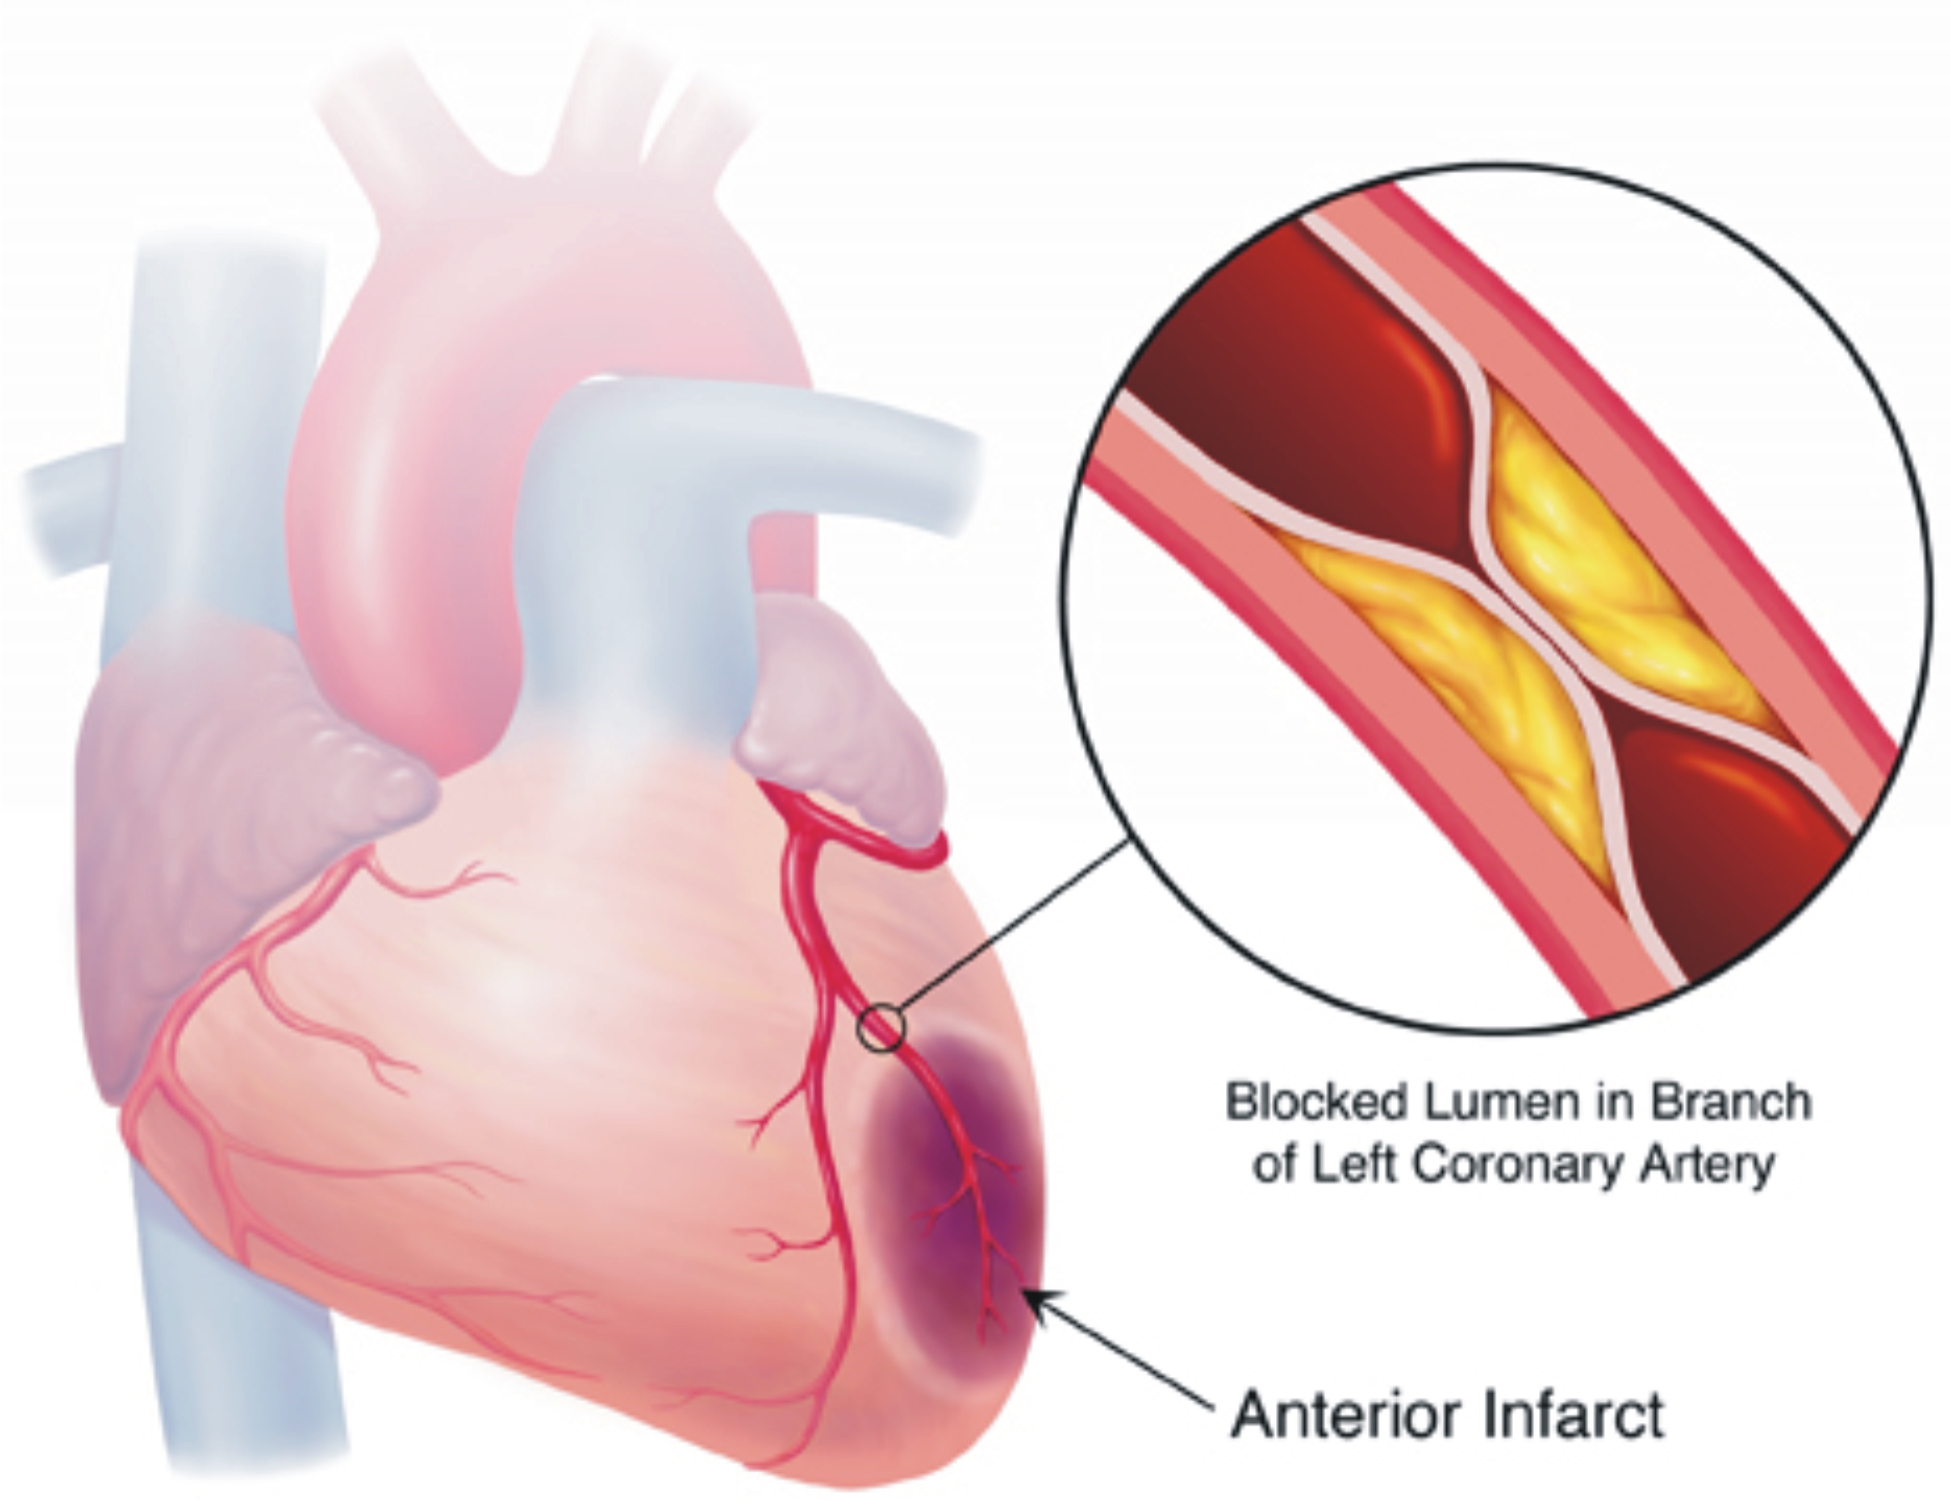

Ischemia is an insufficient supply of blood to an organ usually due to a blocked artery Myocardial ischemia is an intermediate condition in coronary artery disease during which the heart tissue is slowly or suddenly starved of oxygen and other nutrients Ischemia means that there is a reduced blood and oxygen supply to a certain part of the body Locations in the body this condition can affect include the heart intestines brain and limbs Ischemia can happen due to structural or functional problems in the heart but it can have a variety of causes

Ischemic heart disease is heart damage caused by narrowed heart arteries Ischemic heart disease can cause chest pain or discomfort Silent ischemia is when blood flow to the heart is reduced with no obvious symptoms What is myocardial ischemia Myocardial ischemia or cardiac ischemia means your heart muscle is not getting enough blood which contains oxygen and nutrients to work as it should If this lack of blood from your coronary arteries is severe or goes on for more than a few minutes it can damage your heart muscle

Ischemia Meaning - Ischemia is an insufficient supply of blood to an organ usually due to a blocked artery Myocardial ischemia is an intermediate condition in coronary artery disease during which the heart tissue is slowly or suddenly starved of oxygen and other nutrients